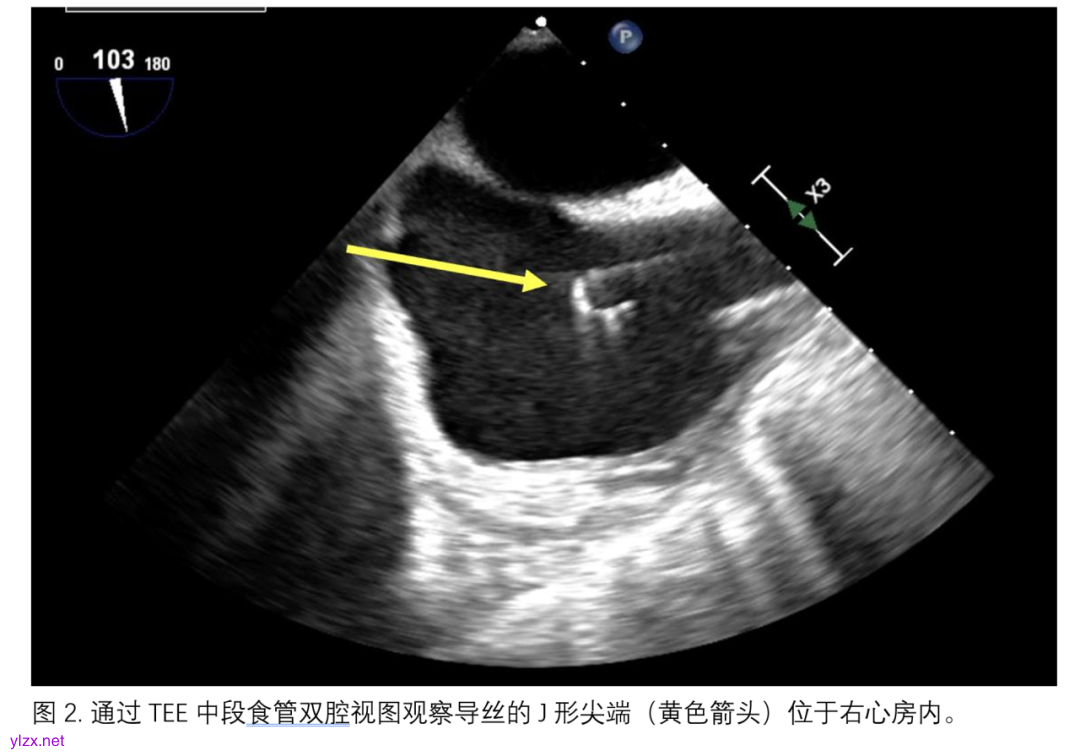

双腔插管的放置可以在透视或经食管超声心动图引导下进行。通过透视确认插管标记指示的流出部位。然而,经食道超声心动图已被很好地用于指导双腔插管的位置,特别是在特殊人群(如COVID-19患者)中,可以避免将患者转运到透视室,并尽量减少对医务人员的暴露。经食道超声心动图的引导是通过中段食管双腔或改良双腔切面实现的。导丝的J形尖端必须被可视化,通过并终止于肝静脉段的下腔静脉,避免进入肝静脉分支或意外进入右心室(图2)。放置位置可以通过在上腔静脉和下腔静脉的插管引流孔处显示湍流,以及通过湍流流出的“射流”指向三尖瓣,且在右心房内几乎没有发散或旋转来进一步确认(图3),以避免诸如心内损伤/右心室穿孔、肝淤血、再循环或结构损伤等并发症[20]。通过对比超声心动图提供高分辨率的影像,可以进一步确认最佳的流动方向,尤其是在有显著肺部病理的患者中,但临床应用比较少。